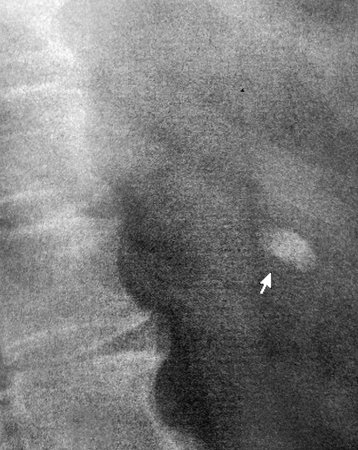

Камень верхней чашки левой почки

Мужчина средних лет